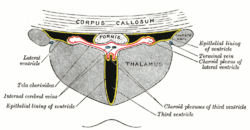

Coronal section of brain through intermediate mass of third ventricle. Coronal section of lateral and third ventricles.

Coronal section of lateral and third ventricles. Central part and anterior and posterior cornua of lateral ventricles exposed from above.

Central part and anterior and posterior cornua of lateral ventricles exposed from above. Tela chorioidea of the third ventricle, and the choroid plexus of the left lateral ventricle, exposed from above.

Tela chorioidea of the third ventricle, and the choroid plexus of the left lateral ventricle, exposed from above. Diagram showing the positions of the three principal subarachnoid cisternæ.